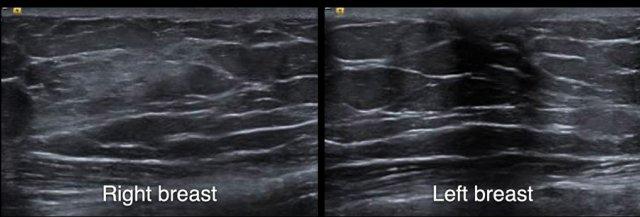

Người phụ nữ này có nhiều nang nhỏ ở cả hai vú.

Các nang này không sờ thấy được.